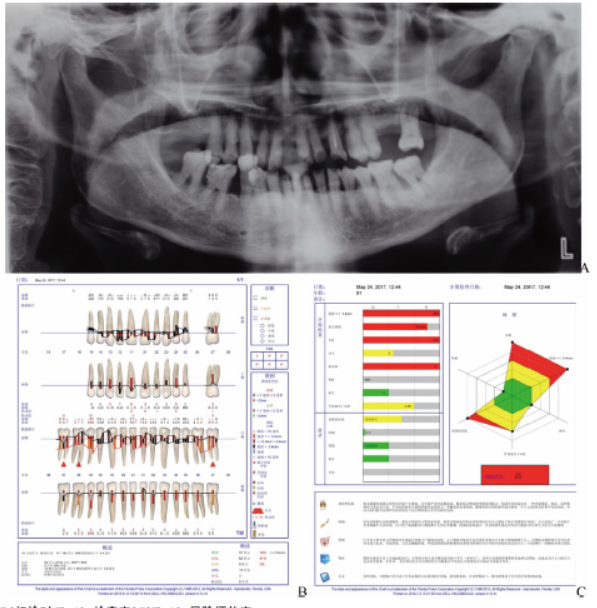

心脏移植后药物性牙龈肥大一例

病史摘要:61岁女性患者,主诉全口牙龈肿胀增厚8个月影响咀嚼。1年前行心脏移植手术,术后服用环孢素A一年,无其他系统性疾病,有青霉素过敏史。诊疗过程:口内检查发现口腔卫生差,牙龈增生等多种问题,口外检查面部对称等,辅助检查有牙槽骨吸收等情况。血清CsA药物浓度142ng/mL,心脏彩超示左室心肌肥厚。诊断为牙周炎(Ⅲ期,B级)、药物性牙龈肥大等多种病症。治疗计划包括口腔卫生宣教、牙

牙列缺损

深龋

药物性牙龈肥大

精粹

典型

浏览 1357 | 讨论 0